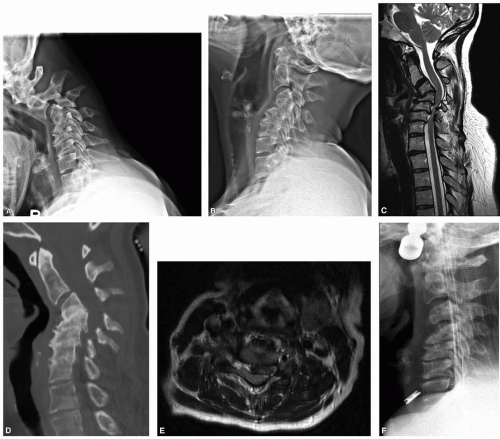

A 43-year-old woman with cervical myelopathy and deformity. There is retrovertebral cord compression behind C4, and disk-based spinal cord and root compression at C5-6 and C6-7, associated with significant cervical kyphosis. The patient was placed in preoperative cervical traction to improve alignment (Figure 2-1).

In general, we have a low threshold for obtaining preoperative CT scans in corpectomy patients (Figure 2-2).

Determine whether areas of deformity are fixed or flexible (eg, if fusion exists across disk spaces and/or facets). For flexible deformities, consider use of preoperative traction for gradual deformity correction. Our case appeared stiff, but clearly demonstrated mobility with traction.